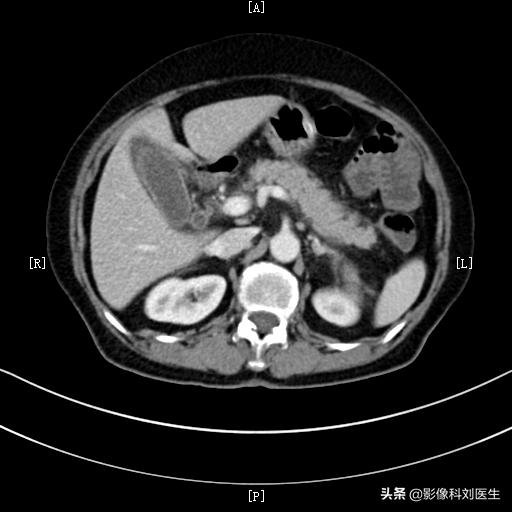

3、腹部CT检查。是诊断胰腺炎最重要的影像学检查。它可以观察胰腺肿大的情况,胰腺周围的渗出情况,通过三期增强扫描,可以判断胰腺组织内是否有坏死,周围是否有假性囊肿形成等。通过CT检查,可以明确急性胰腺炎的分型,了解其并发症情况,对其严重程度进行分级,所以是诊断急性胰腺炎的最佳方法。

正常胰腺